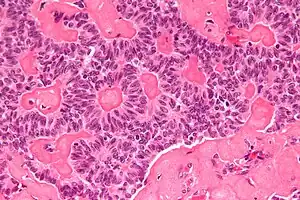

性腺肿瘤伴有环形小管

中度显微镜

高度显微镜